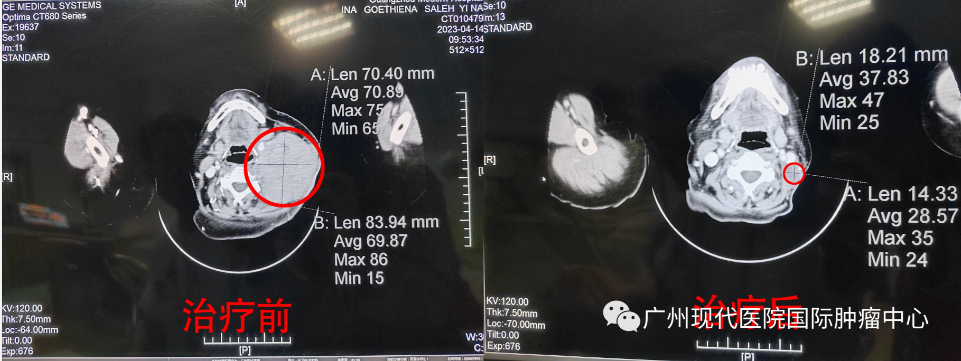

5月7號(hào),醫(yī)生按照既定的治療方案,為依娜進(jìn)行了第2輪的動(dòng)脈灌注介入治療,29號(hào)做CT檢查評(píng)估,結(jié)果顯示左頸部腫塊影(20X35mm),較前明顯減小,左頸內(nèi)動(dòng)脈受壓內(nèi)移較前緩解;原右肺中葉少許斑片影,現(xiàn)已消失。對比4月來院治療前的CT顯示結(jié)果(頸部淋巴瘤大小86X63mm),計(jì)算腫瘤縮小87%,頸部腫塊肉眼看幾乎已經(jīng)消失。